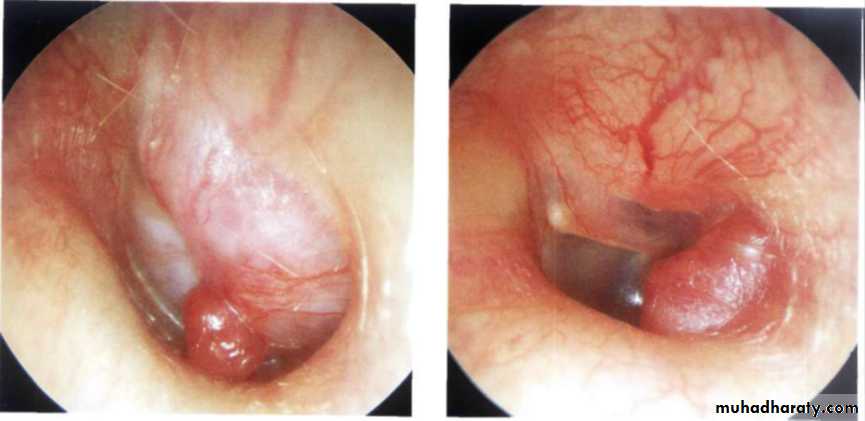

Squamous cell carcinoma

it is seen in cases of long-standing ear discharge.

It may arise primarily from the meatus or be a secondary extension from the middle ear carcinoma.Presenting symptoms are: blood staining of mucopurulent or purulent discharge and severe earache.

Examination may show an ulcerated area in the meatus or a bleeding polypoid mass or granulations.

Facial nerve may be paralysed because of local extension of disease.

Regional lymph nodes may be involved.

Treatment is en bloc wide surgical excision with post-operative radiation.